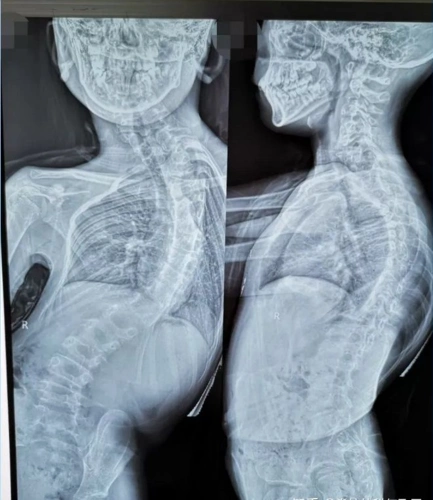

样(俗称高低肩),驼背(对,驼背可能是脊柱侧弯导致的),一侧肩胛骨突出